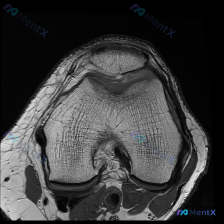

看到这个读片病例,感觉很有代表性,整理了资料和分析思路分享给大家。 病例影像基本信息 本次为膝关节MRI T2序列轴位影像,扫描层面位于股骨髁水平,可见髌骨及股骨滑车关节面,影像所见整理如下: 1. 骨骼软骨:股骨髁骨皮质连续,未见骨折;髌骨形态骨髓信号基本正常;髌股关节软骨信号均匀,轮廓基本连续,...

刚看到这个有意思的影像病例,整理一下完整资料和分析思路给大家参考。 病例基本信息 这是一张膝关节MRI T1加权轴位扫描影像,核心问题是:临床提示存在「软骨异常」,需要解读影像表现并分析原因。 影像客观评估结果 先给大家说客观的影像发现: 1. 骨性结构:股骨远端滑车、髌骨的骨皮质完整,松质骨髓信号...